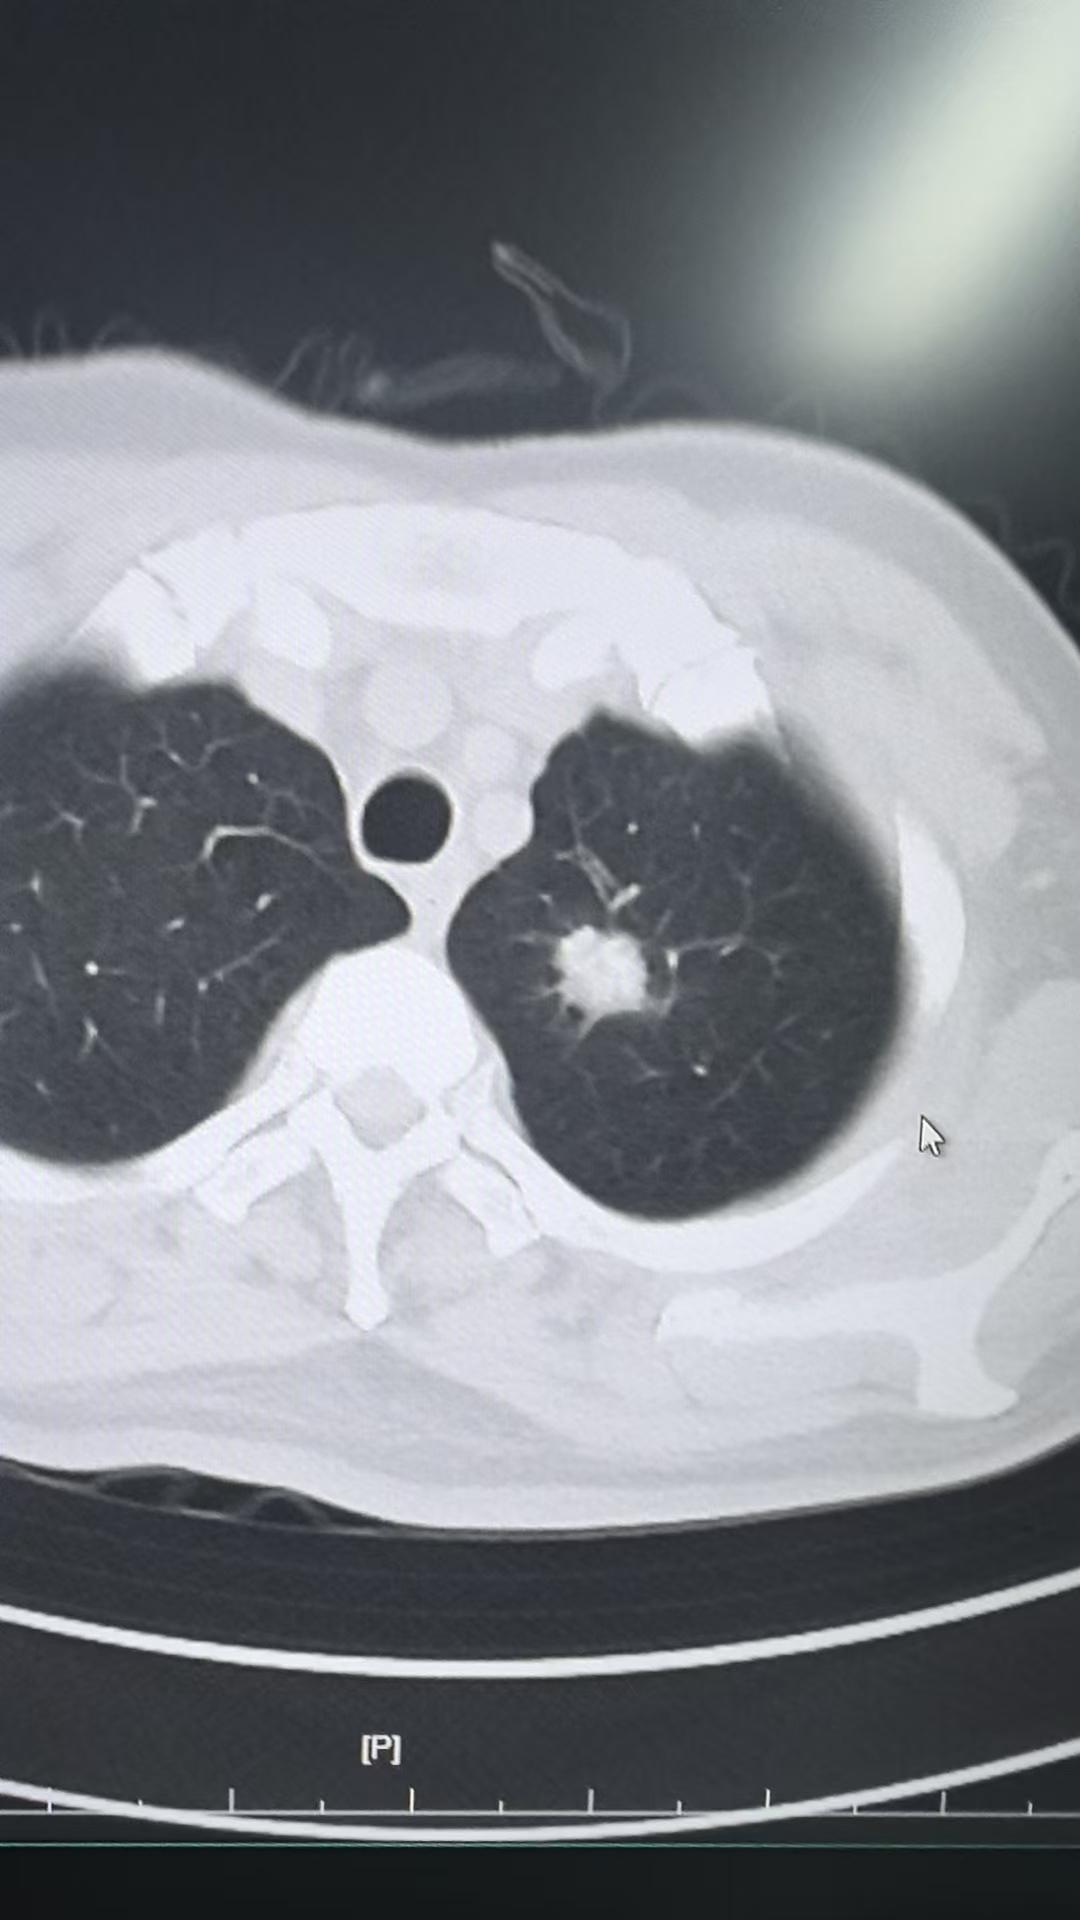

左下肺实性肺癌。左下肺实性肺癌,清扫了第4-14组淋巴结……对于实性的...

这个8mm的微浸润腺癌,看了很多地方没看出来,我们团队没有漏掉这个恶性...